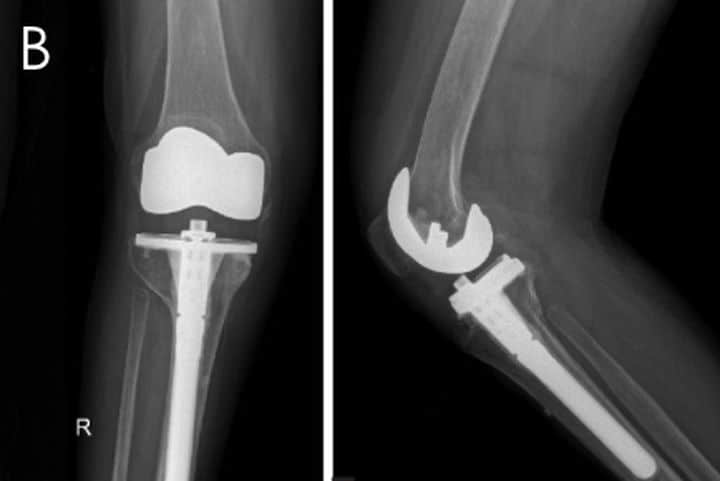

对于已经进展至骨性关节炎的病人,可采用:非手术治疗 + 手术的阶段化治疗。非手术治疗方式包括:物理治疗,改变生活方式(如减轻体重,减少关节活动),口服或注射药物(如止痛药物、软骨保护药物等)。手术治疗方式包括:截骨矫形及关节置换 (图6)。

图6:截骨矫形(A);膝关节置换(B)。